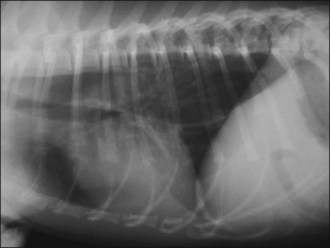

Plain thoracic radiographs (typically right lateral and dorsoventral (or left lateral) views) are useful in animals with regurgitation and may help to identify megaoesophagus, radiopaque oesophageal foreign bodies, aspiration pneumonia and mediastinal masses (Figures 22.1-22.3).

Figure 22.1 Right lateral thoracic radiograph in a dog showing megaoesophagus secondary to myasthenia gravis.

Megaoesophagus is usually readily diagnosed by plain radiography although occasionally a contrast study may be required (see Figure 22.1). The dilated oesophagus may be filled with air, fluid or ingesta. As described above, aspiration pneumonia is the most common complication of megaoesophagus and may be detected radiographically. Once the diagnosis is made, additional tests are indicated to screen for a primary underlying cause.

Sedation and general anaesthesia can both cause oesophageal relaxation that may be misdiagnosed as megaoesophagus on plain thoracic radiographs. If megaoesophagus is considered a significant possibility, radiographs should be taken without sedation.